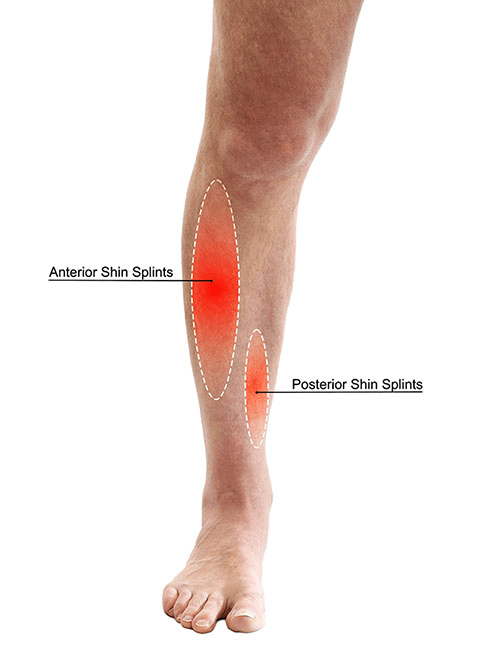

Stage 1 of Shin Splints: Pain occurs after activity and disappears with rest and warm-up (Muscle Pain). 3 words

Mild Muscle Strain

Stage 2 of Shin Splints: Pain occurs before and after activity but does not significantly affect performance (Muscle Pain). 3 words

Moderate Muscle Strain

Stage 3 of Shin Splints: Pain occurs before, during, and after activity, affecting performance (inflammation of the outer covering of the bone). 1 word

Periostitis

Stage 4 of Shin Splints: Pain is severe, constant, and may make activity impossible. Pinpoint pain on the bone. 2 words

Stress Fracture